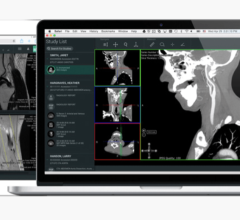

Vitrea software is Vital Images’ advanced visualization solution that creates 2D, 3D and 4D images of human anatomy from CT and MR image data. With this productivity-enhancing tool, physicians can easily navigate within these images to better understand disease conditions. The Vitrea software addresses specialists’ needs through various software options for cardiac, colon, vessel probe and other applications. In addition, Vitrea software utilizes an intuitive clinical workflow and automatic settings to improve speed and simplicity. Other capabilities and partnerships with PACS providers expanded physicians’ access to Vitrea software throughout an enterprise.